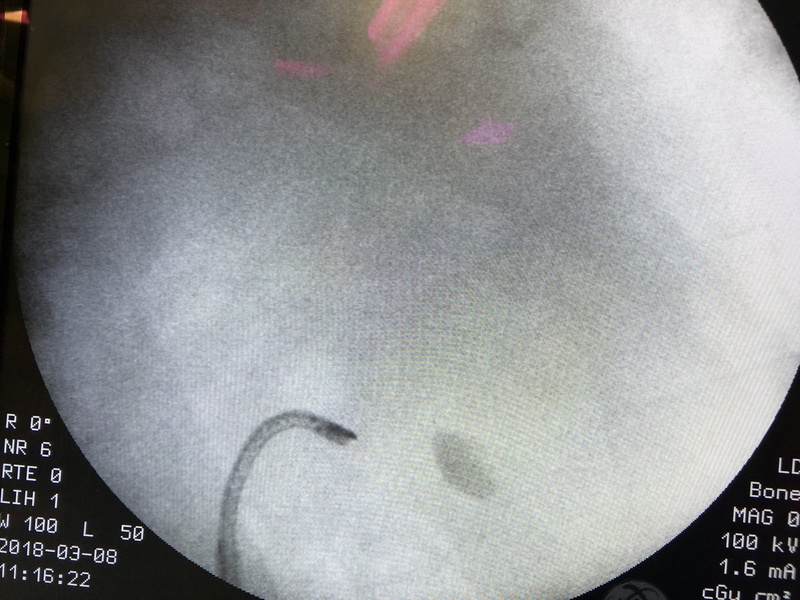

Najnowsza metoda leczenia kamicy nerkowej od dziś dostępna także w Olsztynie. Lekarze Szpitala Miejskiego przeprowadzili pierwszą operację metodą RIRS (Retrograde IntraRenal Surgery).

Wykorzystuje się do tego giętkie przewody wraz z laserem, co pozwala na rozbicie kamieni poprzez naturalną drogę. Metoda jest małoinwazyjna i pacjent jeszcze w dniu operacji może opuścić szpital.